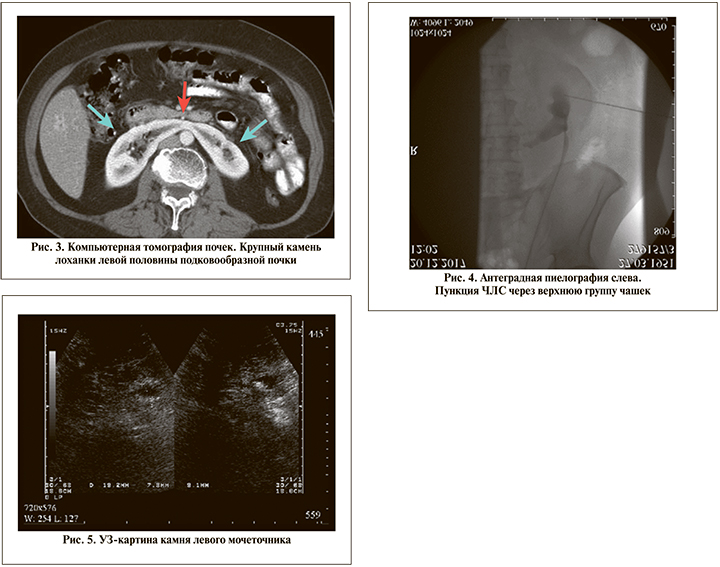

Клиническое наблюдение 2. Пациент Ш. 69 лет. Диагноз: крупный камень (3,5 см) левой половины подковообразной почки. Анамнез: МКБ в течение 12 лет, проявлялась самостоятельным отхождением конкрементов. Обратился к урологу в связи с эпизодической болью в поясничной области слева. В результате обследования диагностирован крупный камень лоханки левой половины подковообразной почки (рис. 3).

Пациенту выполнена малоинвазивная ПНЛТ слева в его положении на животе. Доступ осуществлен под рентгентелевизионным контролем с УЗ-навигацией и использованием допплеровского картирования. Особенностью перкутанного доступа при подковообразной почке является его осуществление через верхнюю группу чашек, что обусловлено наилучшей визуализацией и минимальным расстоянием до чашечно-лоханочной системы (ЧЛС) почки. На рентгенограмме (рис. 4) представлены картина пункции верхней группы чашек и этап формирования доступа в ЧЛС.